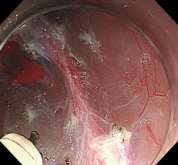

胃内粘膜下隆起,术前超声提示来源于固有肌层,术前判断需胃壁全层切除。

术中所见与术前判断相符,行内镜全层切除术EFTR,术后严密封闭创面,患者2日后安全出院,术后病理诊断胃间质瘤。